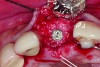

In cases with an incomplete facial plate, the ice cone technique was recommended.20 In this method, a collagen membrane was trimmed to the shape of an ice cone and placed into the socket against the inner aspect of the facial bone. The socket was filled with bone substitutes, and the coronal portion of the membrane was used to cover and protect the underlying bone substitutes. A non-resorbable PTFE membrane can be used for site preservation as well.21 This membrane, if secured to bone, can be left exposed, and epithelialization will occur over it. It was found that sockets grafted with a mineralized bone allograft and PTFE membrane had 47.4% new bone formation and 14.7% residual graft particles. In addition, there was minimum resorption of the buccal bone thickness, as indicated by a 0.3-mm horizontal bone resorption and a 0.25-mm vertical bone resorption.22 A recent systematic review reported that the use of PTFE membranes in ridge preservation shows potential in maintaining ridge dimensions23 and possibly aiding in increasing the zone of keratinized mucosa. Therefore, the use of PTFE membrane may be preferred in ridge preservation of sites in the esthetic zone. Figure 1 and Figure 2 illustrate the use of PTFE membrane in ridge preservation for implant replacement in the esthetic zone. Other authors have also attempted primary closure of the socket or to improve the ridge topography with soft-tissue grafts, but it has not been proven to be effective in increasing bone regeneration.18

In sites with an intact and thick (≥2 mm) buccal bone, no grafting is required. A collagen plug may be used for hemostasis at the site of extraction. In sites with an intact and thin (<2 mm) buccal bone, the mineralized bone allograft-plug augmentation technique is preferred because of its effectiveness. For sites with no or incomplete buccal bone, the PTFE membrane can be placed between the bone and buccal soft tissue to form the buccal border. It is subsequently folded over the entrance of the socket, thus serving to contain and protect the bone graft that is placed into the socket. The PTFE membrane is removed 4 weeks after placement,23 and soft tissue will granulate over the site, thus increasing the soft-tissue thickness, which is beneficial for an esthetic implant restoration. Simultaneous or staged GBR, onlay grafts, ridge expansion, or distraction osteogenesis may be used to further augment the residual ridge if necessary. Soft-tissue augmentation can be performed before ridge augmentation or at implant uncovering stage, depending on the soft tissue thickness and width of keratinized mucosa.

Placement of implant. Notice the bucco-palatal bone thickness gained from the ridge preservation technique.

Figure 2